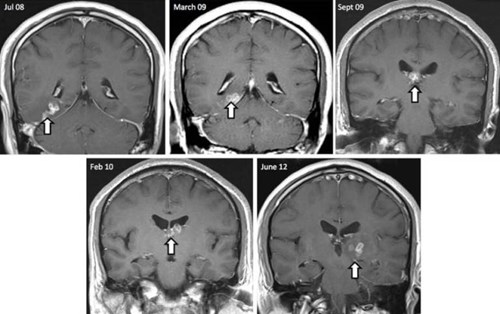

Con sán đã xuất hiện trong hình chụp não bộ của ông Donnelly từ khá lâu.

Donnelly cho biết các bác sĩ đã chẩn đoán ông đang mắc chứng tiền đột quỵ, và ông vẫn tin vào điều đó, cho tới khi phải nhập viện vì một cơn động kinh bất thường.

Một loạt các xét nghiệm đều hướng tới giả thiết rằng ông đang bị khối u não, tuy nhiên một bác sĩ đã tình cờ phát hiện ra một con sán dây bị chết đang mắc kẹt trong não ông.